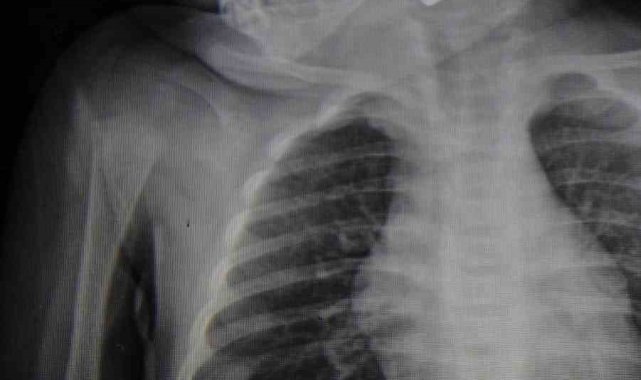

Karaman'da 6 aylık bebeğin boğazına kaçan kumanda pili, ameliyatla çıkarıldı.Edinilen bilgiye göre, kusma şikayeti ile ailesi tarafından Karaman Eğitim ve Araştırma Hastanesi acil servisine getirilen 6 aylık E.A. isimli kız bebeğin, yapılan muayene ve tetkiklerde boğazında kumanda pili kaçtığı tespit edildi. Solunum sıkıntısı da yaşayan bebek hemen ameliyata alındı. Çocuk Cerrahisi Uzmanı Doç. Dr. Mehmet Uysal tarafından yapılan ameliyatla bebeğin boğazındaki pil çıkarıldı."Hemen müdahale ettik"Yaşanan olayla ilgili bilgi veren Doç. Dr. Mehmet Uysal, "Acil polikliniğimize kusma şikayeti ile 6 aylık bir kız bebek getirilmiş ve bize haber verildi. Biz de vakit kaybetmeden geldik, hastamızı gördük. Yapılan tetkikler sonucunda, ağız tabanına oturan ve yemek borusunun birinci darlığına kadar uzanan, kumanda pili dediğimiz bir pille karşılaştık. Filmde ve muayenede bunu gördük. Hastayı ilk gördüğümüzde bayağı siyanotik durumda, solunum sıkıntılıydı ve oksijen satürasyonu 90 civarındaydı. Böyle olunca bir an önce beklemeden hızlı bir şekilde ameliyathaneye götürdük. Orada ameliyathanedeki anestezi uzmanlarımız ve personel bize yardımcı oldu, hasta hızlı bir şekilde entübe edildi. Ondan sonra da laringoskop ve magill forseps dediğimiz malzemelerimizle bu yabancı cismi çıkarmış olduk. Bir an evvel müdahale ettik, iyi ki müdahale ettik, orada ağız tabanında, özellikle ön kısmında hasar oluşmuştu. Müdahale sonrasında da hastanın solunum problemleri bir süre devam etti, bu yüzden 24 saat takip ettik. Herhangi bir problem oluşmayınca 24 saat sonra kontrole gelmek üzere hastayı taburcu ettik" diye konuştu."Aileleri uyarıyoruz"Ailelere uyarılarda bulunan Doç. Dr. Uysal, "Bu konularda aileleri uyarıyoruz. 1 yaş altı çocuklarda bile bu durum oluşabilir. Bazen 2-3 yaş diyoruz ama 1 yaş altındaki çocuklarda da emekleme döneminde bile bu tür yabancı cisimleri, özellikle kumanda pili, kalem pil gibi şeyleri ortada bırakmamak lazım. Çocuklar meraklı olduğu için her şeyi ağzına götürmeye meyilli. Dikkat etmediğimiz takdirde ölümcül sonuçlar oluşabiliyor. Bu vakada şanslıydık, çocuktaki durum erken fark edildi ve hemen müdahale edildi. Şu anda çocuk sağlıklı bir şekilde hayatına devam ediyor" dedi.